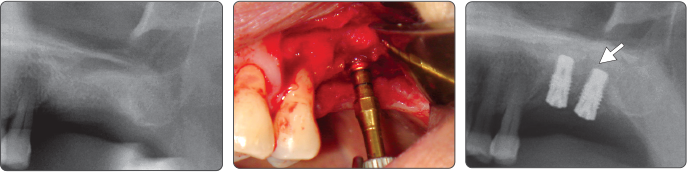

2. Sinus Lift (Ø5.0 Fixture)

▶ Immediate Implantation and Sinus Lift Technique with Tap Drill (Ø5.0 Fixture)